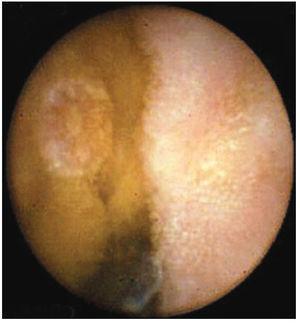

ResultadosEn el periodo comprendido entre enero 2003 a marzo 2008 se realizaron un total de 45 estudios. En 43 pacientes, la cápsula fue deglutida con agua, en dos de ellos tuvo que ser introducida con sobretubo, debido a la incapacidad de los pacientes para deglutirla; procedimientos que se realizaron sin complicaciones y con éxito. El sexo femenino predominó con 27 pacientes (60%) con una mediana de edad de 58.16 años, con intervalo entre los 18 y 84 años. El grupo etáreo más afectado fue el comprendido entre los 71 a 84 años de edad con 14 casos. El motivo de envío más frecuente fue el sangrado gastrointestinal de origen oscuro, con 32 casos (71.11%). Los siguientes fueron diarrea crónica con cinco casos (11.11%), dolor abdominal tres casos (6.67%) y melena tres casos (6.67%). Los hallazgos reportados incluyeron: Sin causa 18 casos (40%), erosiones en 10 casos, algunas de ellas relacionadas con AINE (22.20%) (figura 2). Alteraciones vasculares en ocho casos (17.76%), pólipos en seis casos (13.32%), gastropatía nodular con dos casos (4.44%), tumoraciones en dos casos (4.44%) (figuras 3 y 4), y con un caso (2.22%) cada una de las siguientes patologías: pseudopoliposis antral, diverticulosis y sangrado activo en el Treitz de causa no determinable. En general, el procedimiento fue bien tolerado. No se presentaron complicaciones durante ni posterior al procedimiento. No se reporta en ningún caso la retención de la cápsula en el tubo digestivo. Mención aparte, aunque no fue motivo del presente estudio, será importante contar con el número de pacientes que fueron sometidos a estudios complementarios (serologías, enteroscopias, laparotomías, etc.), ya que con ello se podrán tener más argumentos para definir el lugar que actualmente ocupa la videocápsula en nuestro país y tal vez con más investigación de este tipo, poder sugerir un algoritmo de estudio para pacientes con hemorragia de origen oscuro.

Figura 2. Erosión en yeyuno por AINE.